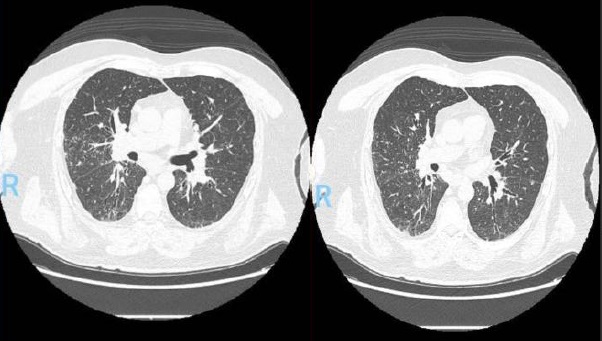

En la tomografía computada de tórax en ventana pulmonar se identifica un patrón micronodular con distribución perilinfática y difusa en ambos hemitórax. Este hallazgo se acompaña de un engrosamiento peribronquial notable, así como de opacidades en vidrio deslustrado, que predominan en las zonas subpleurales y en las regiones posteriores de ambos pulmones.

En la tomografía computada de tórax en ventana mediastínica se observan múltiples adenopatías localizadas en diversas áreas del cuello y mediastino. Estas adenopatías se distribuyen en las cadenas yúgulo-carotídeas, en ambas regiones supraclaviculares y a lo largo del mediastino, abarcando específicamente las siguientes áreas: la región paratraqueal superior derecha, los espacios retrocavo-pretraqueal y prevascular, la zona subcarinal, la ventana aortopulmonar y en la región de la arteria mamaria (AM). La presencia de estas adenopatías sugiere un compromiso linfático difuso en estas zonas.